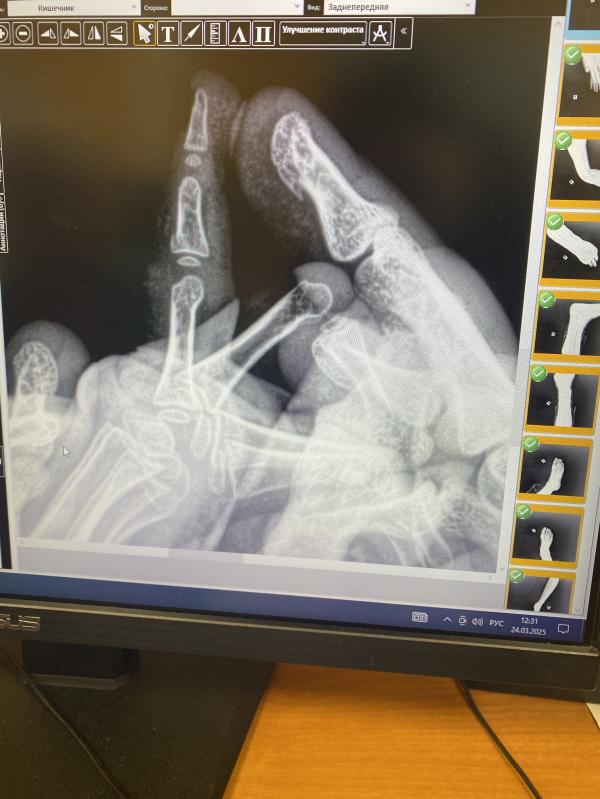

Трещина в мизинце у ребёнка: что делать маме?

Сын защемил палец в двери, сказали трещина

Защемил мизинец